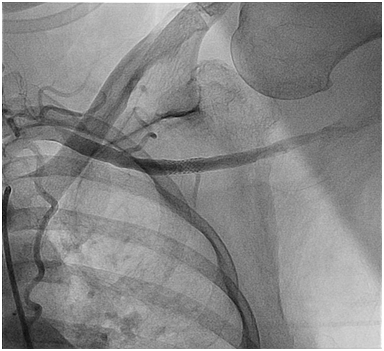

One clinical implication of the ubiquitous nature of Type III arches in our very elderly aortic stenosis patients relates to percutaneous access for interventions such as TAVR. In specific, with the left arm hyper extended over the head, the trajectory of the left axillary and left subclavian arteries falls along the trajectory of a Type III arch (Figure 3). This trajectory makes an axillary approach an attractive alternative to trans: apical and trans: aortic approaches in patients with advanced lung disease or severe peripheral artery disease (PAD) who are not good candidates for either transfemoral or transapical/transaortic approaches. Finally, this information coupled with the fact that axillary artery size is quite comparable to femoral artery size in most patients,8,9 a totally percutaneous left axillary artery approach utilizing a double Per close large bore arteriotomy closure at the end of procedure is highly feasible for a totally percutaneous TAVR as demonstrated by Shäfer et al.10 and also for totally percutaneous Impella device insertion and removal (Figures 4A to 4E) as shown by our group.8

Figure 4C Final L axillary artery Angiogram post a totally percutaneous closure of the large bore arteriotomy at the end of the high risk PCI procedure.